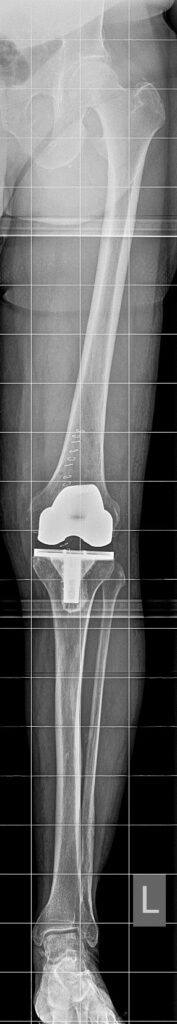

Pangonarthrose: Bei dieser schwerwiegendsten Form sind alle Gelenkkompartimente vom Verschleiß betroffen. Die Symptome sind entsprechend ausgeprägter und die Behandlung komplexer.

Röntgenbild einer schwerwiegenden Arthrose im Kniegelenk mit nahezu aufgebrauchten Gelenkspalt innen- und außenseitig (Pangonarthrose)